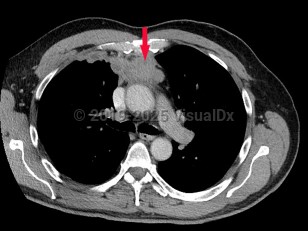

Rare tumor of the thymus, arising in the anterior mediastinum from thymic epithelial cells and lymphocytes. Mostly benign, but with a malignant and metastatic form. Onset is typically in the fifth and sixth decade; it rarely occurs in children. Associated disorders include myasthenia gravis (30%), pure red cell aplasia, hypogammaglobulinemia (Good syndrome), and other systemic diseases. Associated with autoimmune disease in approximately 40% of diagnosed adults. Signs and symptoms associated with tumor growth include neck mass, dyspnea, cough, chest pain, and muscle weakness.